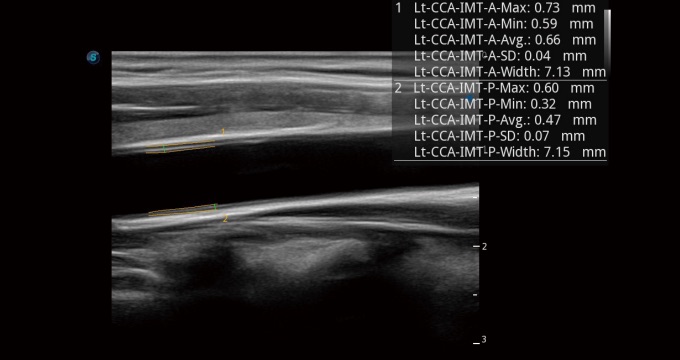

血管内中膜的厚度值是预测心血管疾病风险的重要指标,Auto IMT可以实现血管近场和远场内中膜厚度的自动测量,为临床提供快捷有效的诊断工具。